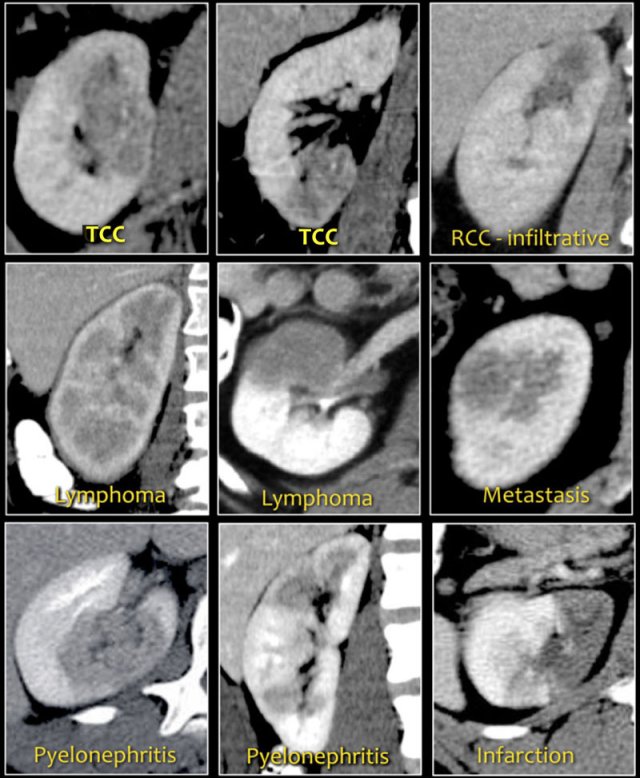

Bean-type lesions

The radiologic features of bean-type lesions are generally nonspecific.

Notice the similar appearance of the lesions in the figure.

The differential diagnosis can often be suggested by integrating clinical and imaging data.

- A central infiltrating lesion that fills the renal pelvis in an older patient is most likely a transitional cell carcinoma (TCC), also called urothelial cell carcinoma (UCC).

- An infiltrative mass in a young patient with sickle cell trait is likely to be renal medullary carcinoma.

- Multifocal and bilateral lesions or diffuse renal infiltration in combination with lymphadenopathy and involvement of other organs is suggestive of lymphoma.

- Multifocal and bilateral renal lesions in known malignancy is suggestive of metastases, although in case of a single infiltrative mass, infiltrative renal cell carcinoma must be considered.

- In patients with pain and signs of infection, the diagnosis is pyelonephritis.

- Wedge-shaped lesions are suggestive of infarction.